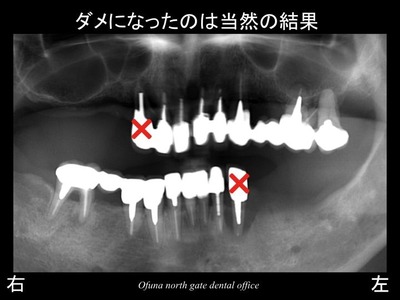

ダメになったのは、当然の結果だったのです。

神経がないことは、今後悔しても しかたがないことです。

もう一度神経が蘇るわけではありません。

それよりも 今後被害を拡大させないことです。

治療計画は、患者様のご希望も含めて以下のようになりました。

1.×印の歯は抜歯!

2.欠損部は、インプラント治療を行う!

3.噛み合わせの治療と虫歯の治療のため、全ての被せ物を撤去し、

新しく作成する。